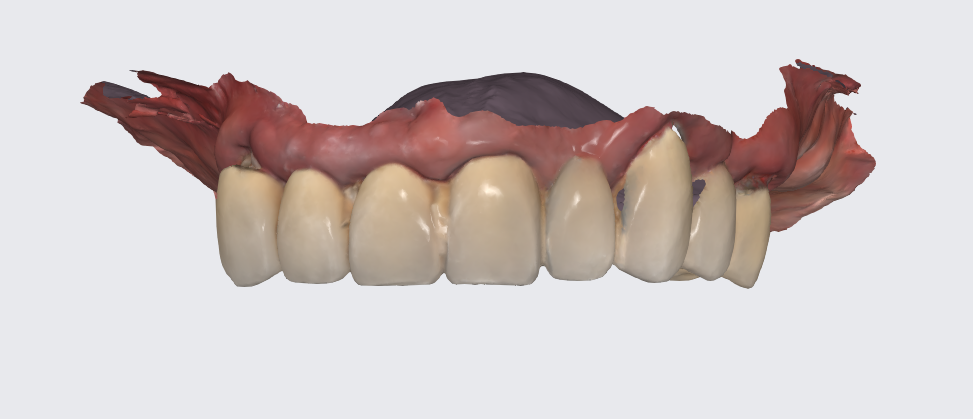

To prepare for the maxillary all on X procedure patient had the upper denture relined with impression material and also multiple dots of radio opaque filling material where temporarily placed on the said denture. Then the 2 dentures where scanned. Also scans of the healed tissues and of the face where recorded.

Shining 3D Metismile face scanner was used to perform the face scan and also alignment of intra oral data with the said face mesh. With the new updates teeth color is corrected on the intra oral scan to match the one recorded by the Metismile so that a more coherent look can be generated. Lip contour was automatically removed from the face scan after data matching.

A new waxup was generated in Exocad and printed as a try in to check occlusion but also esthetics at some degree and have a proprosthetic implant positioning available in the planning step.